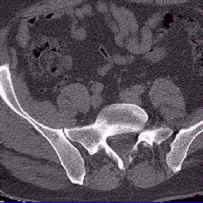

Para obtener los cortes sagital y coronal se pulsará con el ratón en la imagen axial, aparecerá dos ejes que se corresponden con los cortes mostrados. Es posible ver las imágenes reconstruidas a tamaño real haciendo doble clic sobre ellas.

Reconstrucción del corte Sagital

Recostrucción del corte Coronal